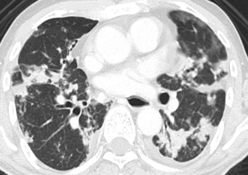

CT θώρακα. Θολερές αναλαμπές τύπου «θαμπού υάλου» (Ευγενική παραχώρηση Dr. V. Penopoulos)